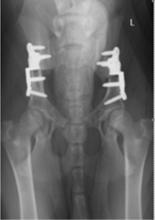

犬髖關節發育不良早期干預治療是建立在早期診斷的基礎上的手術治療,現在公認比較有效的早期治療方式包括了3.5-4.5月齡進行幼犬恥骨聯合吻合手術(juvenile pubic symphysiodesis,JPS) ,5-8月齡進行骨盆兩刀切(double pelvic osteomy,DPO) /骨盆三刀切手術(triple pelvic osteotmy,TPO)。其中DPO手術是義大利的獸醫在2006年首次報導的,這個手術改進了傳統的骨盆三刀切手術帶來的骨盆狹窄與坐骨面提升的併發症。

犬髖關節發育不良後期治療包括使用股骨頭頸切除手術( femoral head and neck ostectomy ,FHO)和犬全髖關節置換手術(total hip replacement THR)。使用股骨頭切除手術是一種通過股骨頭切除使得髖關節不會磨損和疼痛的手術,是在1965年開始使用的一種技術,至今仍被使用。有德國獸醫在1978年到1989年歸納總結了132隻狗和51隻貓進行FHO之後的情況,總結結果認為有83%的病例有腳變短的情況,75%的病例有肌肉萎縮,74%的病例有降低後肢伸展範圍,56%的病例有跛行,32%的病例在伸展腳的時候有疼痛反應,有10%的病例有關節捻發音。這這些病例中,只有少數的犬體重高於15kg,體重大的動物術後效果會變得更差。儘管如此,有78%的寵物主人仍然覺得這個手術的效果是可以接受的。 而在80年代開始出現了全髖關節置換手術(THR),最終在90年代變得相對成熟,在2000年後在歐美,這個手術已經廣泛被人接受。這個手術的成功率約95% 與人的全髖置換成功率相當,關節假體能使用15年以上,基本能滿足犬一生的使用需求。